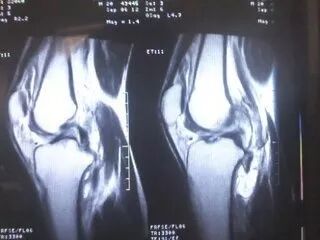

膝关节的疼痛与治疗

膝关节由股骨下端、胫骨上端和髌骨构成,是人体最大最复杂的关,属于滑车关节。它所受到的应力大,结构稳定而又灵活。膝关节疼痛时有发生,而这种疼痛往往被忽视或者被人们武断地认为是关节炎等病症。其实,导致膝关节疼痛的原因有很多。膝关节病主要包括:骨性关节炎、滑膜炎、半月板损伤等。